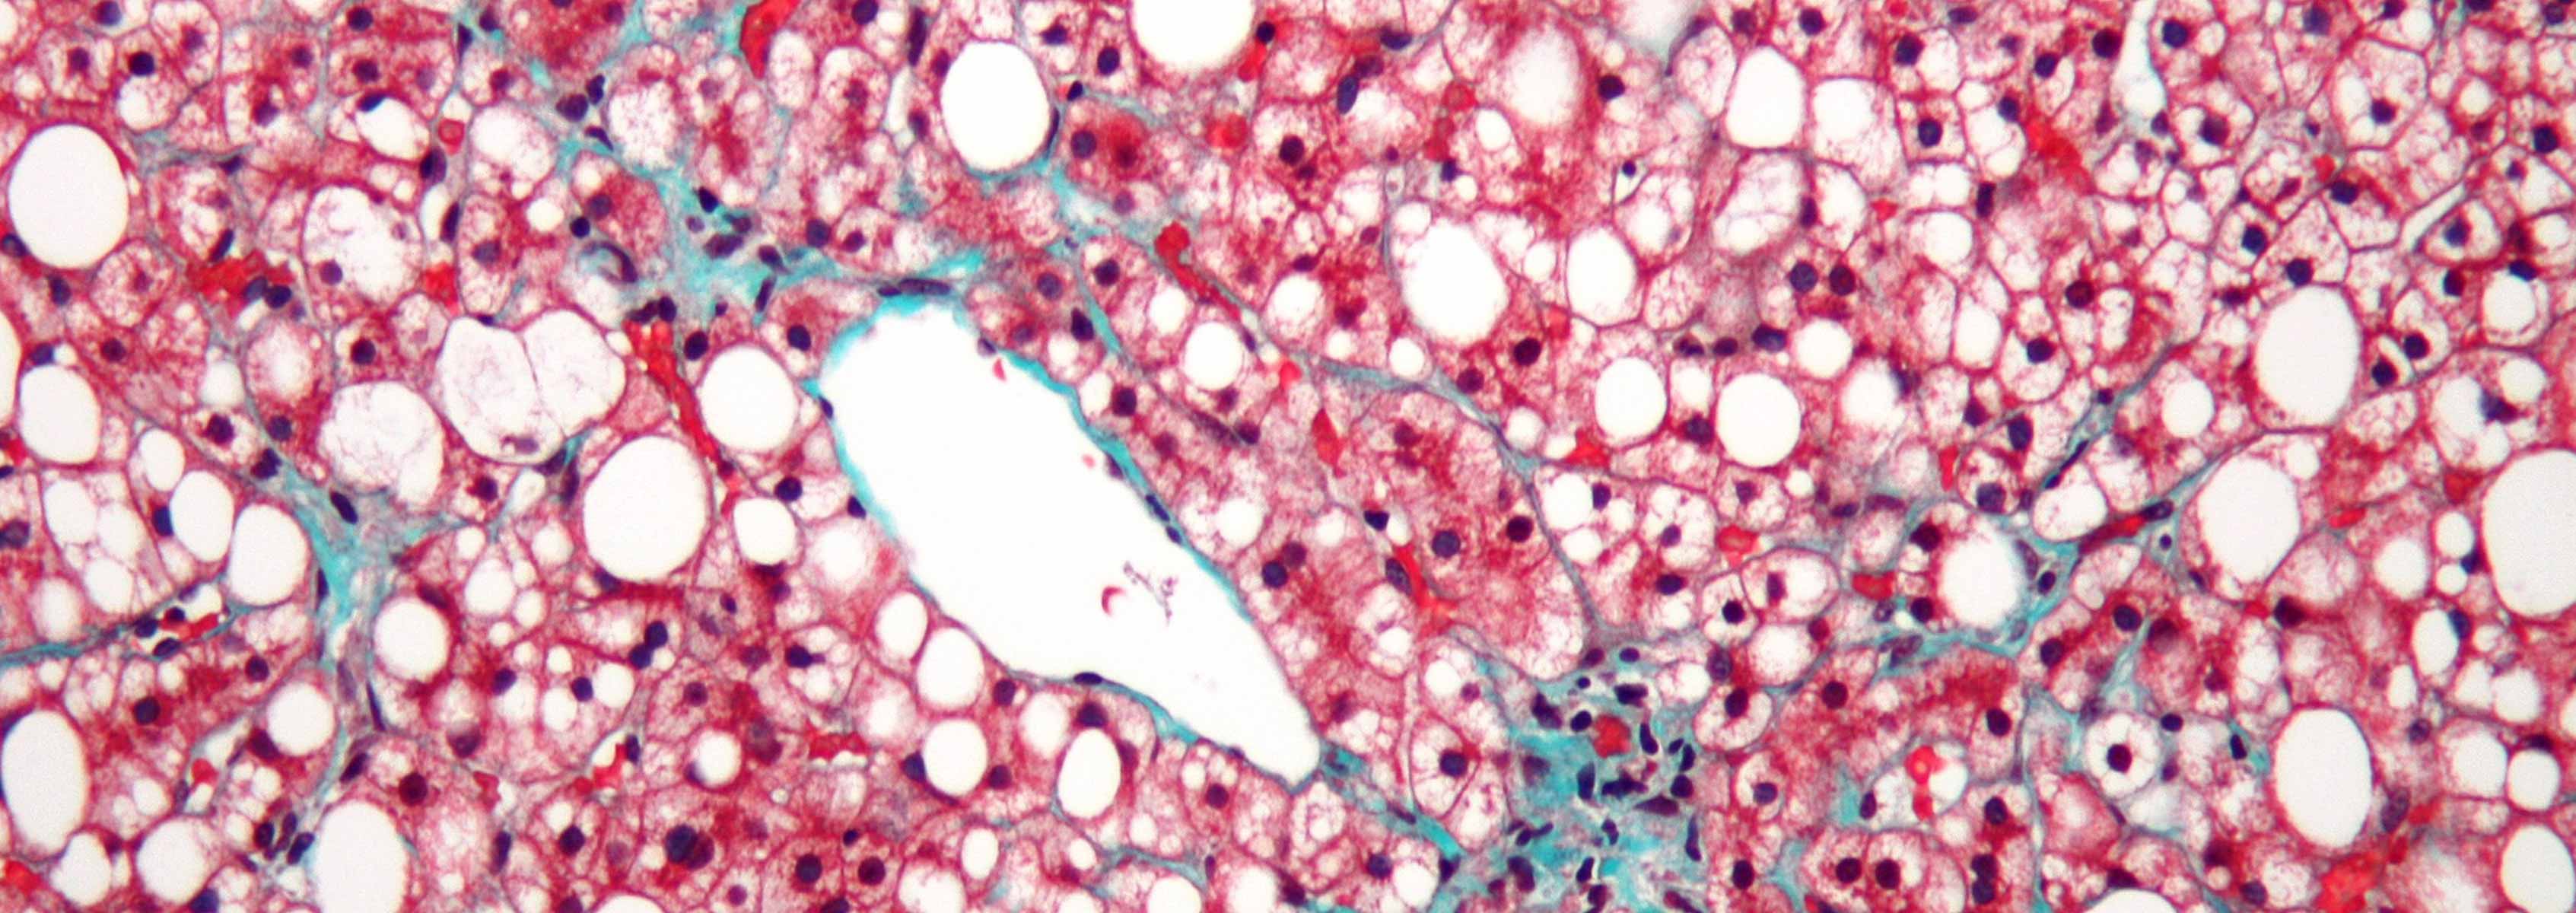

In the second study, published in J. of Hepatology, intestinal permeability, bacterial translocation, and the intestinal microbiome were studied in two mouse models of liver disease; cholestasis and toxic liver injury. Microbiome data was also compared between four different mouse models of liver injury. Ligation of the common bile duct (BDL), modeling cholestatic liver injury, resulted in a rapid onset of bacterial overgrowth; however, it took 24 injections of carbon tetrachloride (CCl4), modeling toxic liver injury, to observe bacterial overgrowth. Though there were differences in the timing of bacterial overgrowth between these two mouse models, an increase in intestinal permeability and bacterial translocation was observed in both models in just one day following treatment. These increases were accompanied by disruption of tight junctions and a decrease in expression of the tight junction protein occludin. Analysis of the intestinal microbiome, targeting the 16S rRNA gene, revealed minor changes following BDL, but major changes following CCl4. Specifically, there was an increase in the relative abundance of Firmicutes and Actinobacteria in treated compared to untreated mice. Shannon and Simpson indexes indicated a decrease in bacterial diversity in the CCl4-treated group. Comparison of microbiome data from the alcohol model, BDL, CCl4, and an obesity model noted that there was no common liver disease microbiome, suggesting that the intestinal microbiome differs by etiology of liver disease.